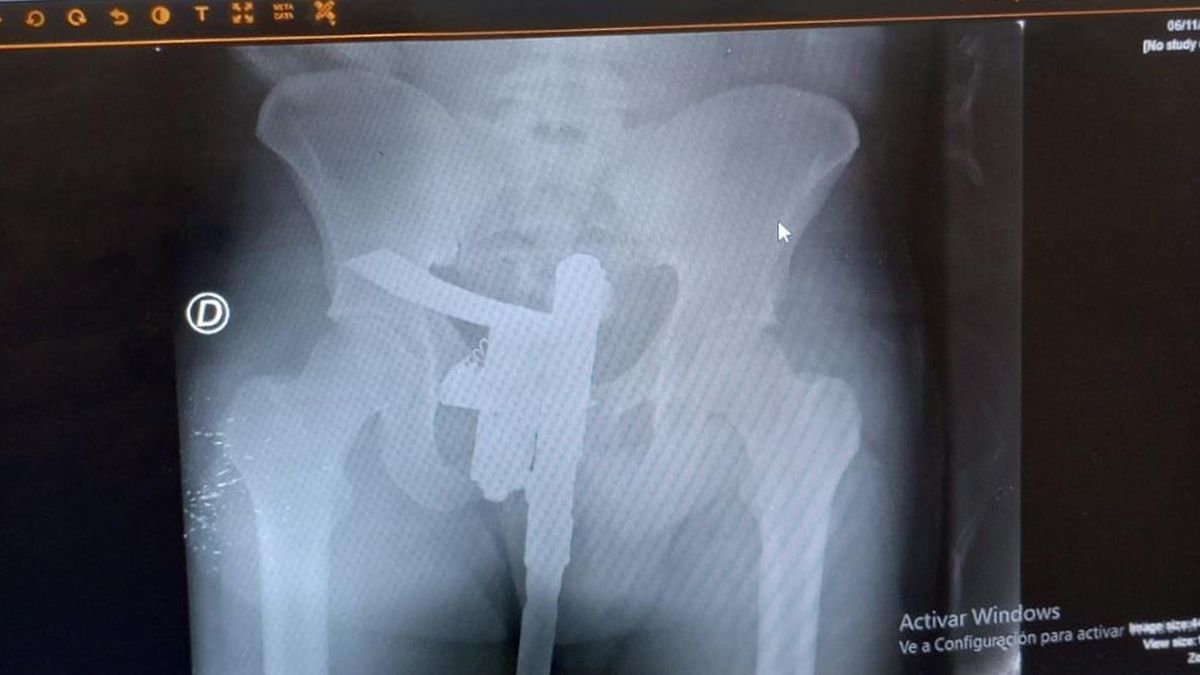

Al llegar al centro de salud, el sujeto fue asistido por los médicos de emergencia y derivado al área de rayos x en donde le realizaron las placas para determinar cómo estaban sus huesos a raíz del accidente.

Sin embargo, una gran sorpresa se llevó el radiologo que hizo la placa, ya que cuando terminó el estudio y detectó un elemento bastante sugestivo y muy similar a un arma de fuego por lo que convocó al personal del destacamento policial del Cullen que requisó al accidentado y le sacó el armamento.

El arma fue de fabricación casera y según determinó el peritaje realizado por al área de balística de la Agencia de Investigación Criminal se encontraba apta para el disparo pero sin ningún tipo de munición. A raíz del hallazgo, el muchacho quedó detenido y dos días después fue llevado a tribunales en donde se le imputó la tenencia de arma de guerra y luego quedó en libertad.